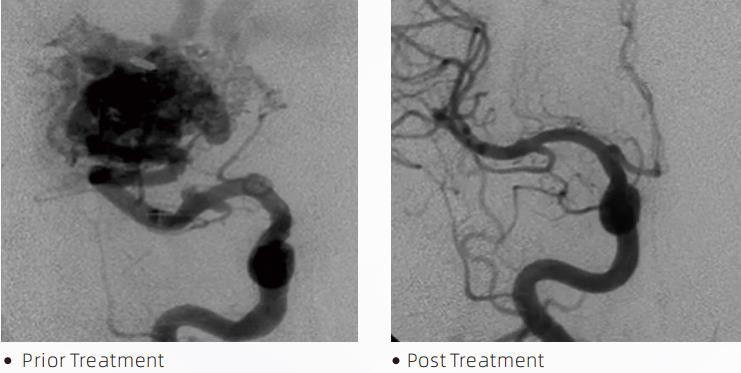

De LavaTMLiquid Embolic System is een interventionele endovasculaire therapie voor de behandeling van cerebrovasculaire malformaties. Cerebrovasculaire malformatie verwijst naar een groep goedaardige of kwaadaardige neurovasculaire afwijkingen die kunnen leiden tot intracraniale bloedingen, herseninfarcten, hersenischemie en andere ziekten. Het vloeibare embolisatiesysteem is een medisch apparaat dat via eenvoudige intravasculaire inbrenging wordt toegediend en dat abnormale cerebrale bloedvaten emboliseert door het injecteren van een speciaal vloeibaar materiaal. Het vloeibare materiaal vormt een gecontroleerde weefselembolie in de bloedvaten, waardoor de impact van cerebrovasculaire misvormingen op patiënten kan worden verminderd. Om toegang te krijgen tot de embolisatieplaats wordt een DMSO-compatibele plaatsingsmicrokatheter gebruikt die is geïndiceerd voor gebruik in de neurovasculatuur. Lava vloeibaar embolisch middel is een niet-klevend vloeibaar embolisch middelsysteem dat bestaat uit EVOH (ethyleenvinylalcohol)-copolymeer opgelost in DMSO (dimethylsulfoxide) en gesuspendeerd gemicroniseerd tantaalpoeder om contrast te bieden voor visualisatie onder fluoroscopie. LavaTMis verkrijgbaar in drie productformuleringen: LAVA-12, LAVA-18 en LAVA-34. LAVA-12: Aanbevolen bij het voeden van distale microvaten en via kleine feeders. LAVA-18: Aanbevolen bij het voeden van pedikelinjecties dicht bij de nidus; LAVA-34: Aanbevolen voor het emboliseren van hogere flow en grotere fistelcomponenten.